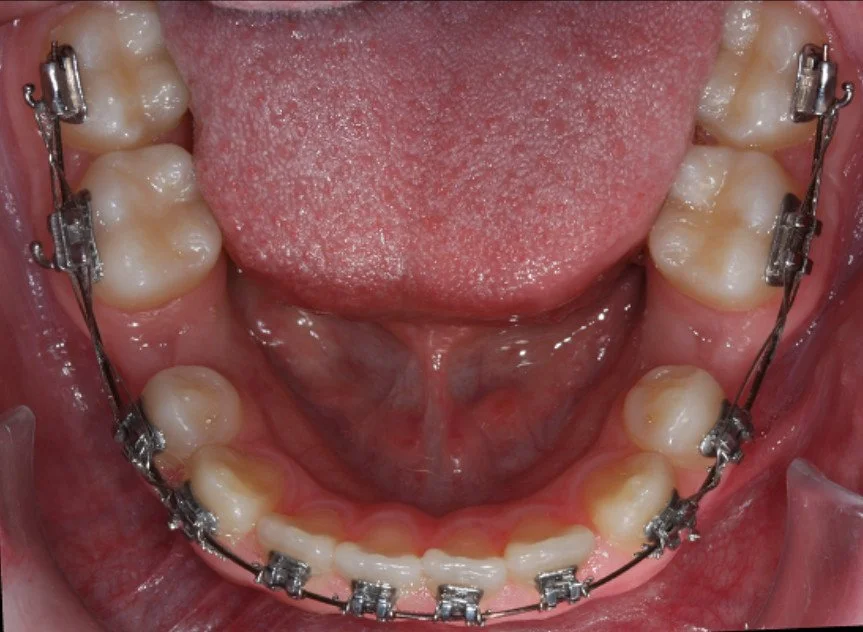

BEFORE

Trattamento con 4 estrazioni di una malocclusione di classe II con proclinazione degli incisivi superiori e inferiori.